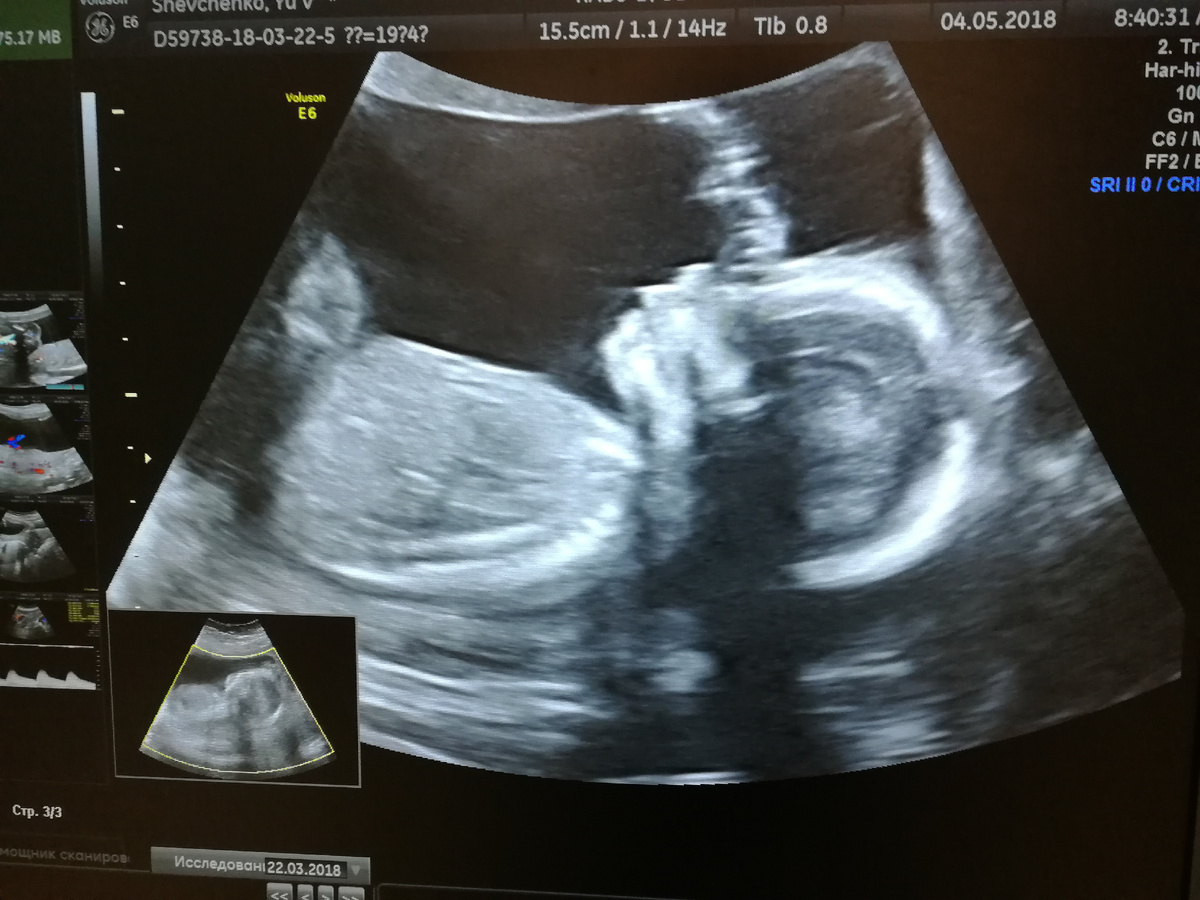

УЗИ в 4-Д. Отчетливое личико. 30 недель беременности.

Мы же узнали, что у нас будет девочка, достаточно поздно - в 30 недель беременности. Наша доченька не хотела показываться. Но решила показаться в мой День Рождения. Сделала маме подарок.